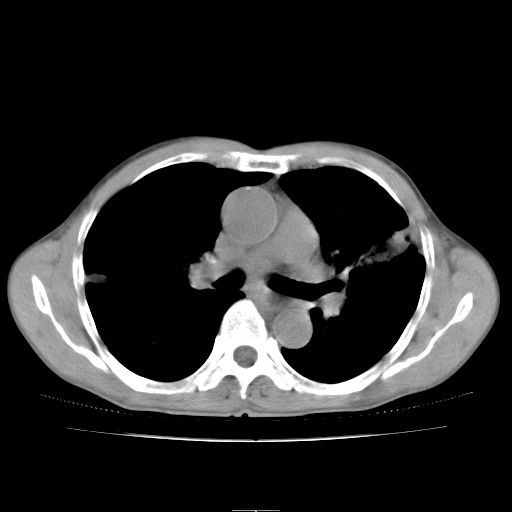

标题: CT25795:感冒后反复咳嗽两月余,痰中带血半月余。X诊断“肺 [打印本页]

标题: CT25795:感冒后反复咳嗽两月余,痰中带血半月余。X诊断“肺

1.双肺肺梗塞(理由:病灶呈三角形,与胸膜相连且局部胸膜肥厚,左心室增大)伴肺感染。

肺梗塞虽然有创意,但不现实。我考虑感染性病灶。

考虑两肺感染性病变,左肺上叶舌段肿瘤性病变待排;建议抗炎治疗后复查。